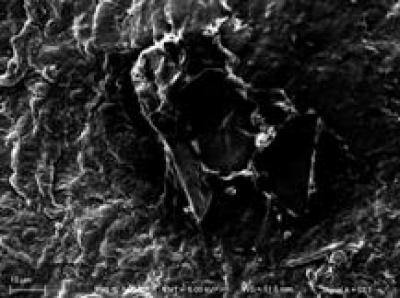

The conventional method for repair of peripheral nerve injury is autogenous nerve grafting, but sources of autogenous nerve are limited. Furthermore, neurological deficits in the donor site and painful neuroma can occur following surgery. The use of allogeneic nerve grafts is limited because of host immune rejection. As reported, tensile stress and tensile strain directly affect the quality of nerve regeneration after bridging nerve defects by poly(lactic-co-glycolic acid) conduit transplantation and autogenous nerve grafting for sciatic nerve injury. A new study published in the Neural Regeneration Research (Vol. 8, No. 21, 2013) showed that, following poly(lactic-co-glycolic acid) conduit transplantation for sciatic nerve repair, the maximum tensile load, maximum stress, elastic limit load and elastic limit stress all increased compared with autogenous nerve grafts, but elastic limit strain and maximum strain decreased. Moreover, the tendencies of stress-strain curves of sciatic nerves were similar after transplantation of poly(lactic-co-glycolic acid) conduits or autogenous nerve grafts. These findings indicate that poly(lactic-co-glycolic acid) conduits are suitable for sciatic nerve injury repair.